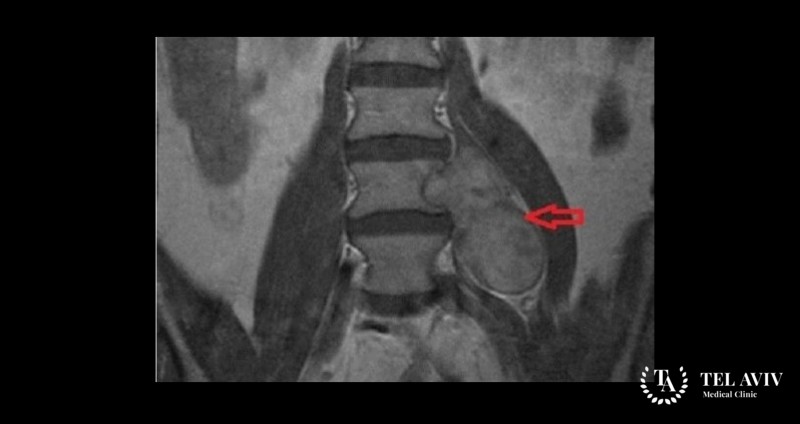

Невринома – является доброкачественным образованием, которое формируется из оболочек периферических нервов. Зачастую патологию врач диагностирует у взрослых в возрасте 40-50 лет. Образование не прорастает в соседние структуры и не дает метастазы. Человек может даже не подозревать о наличии заболевания, так как симптоматика выражена крайне слабо. По мере роста опухоль начинает сдавливать соседние ткани и смещает их в сторону. Болезнь прогрессирует и больной может умереть. Поэтому ни в коем случае нельзя игнорировать проявление опасных симптомов.

- МРТ или КТ;